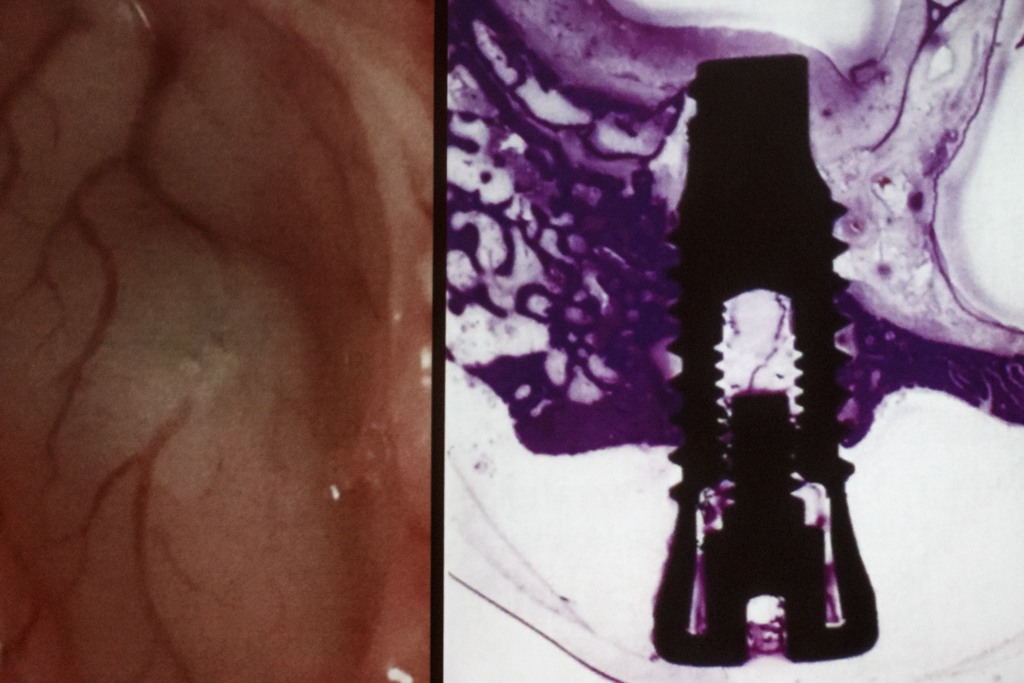

16-17 ноября 2017 года в Учебном Центре "Дентал Гуру" проходил "Продвинутый курс по имплантации". В качестве лектора выступил специалист по костной пластике, эксперт международного исследовательского центра MINEC, опиньон-лидер Impro, MegaGen, установивший более 10.000 имплантатов - Панцулая Виталий Георгиевич.

Участники курса, присутствующие доктора, узнали, как провести диагностику различными методами и составить комплексный план лечения, как выбрать ту или иную методику костной пластики, основываясь на точных критериях, как провести костную пластику безопасно и предсказуемо и эффективно бороться с осложнениями. По итогам курса все участники получили именные сертификаты.